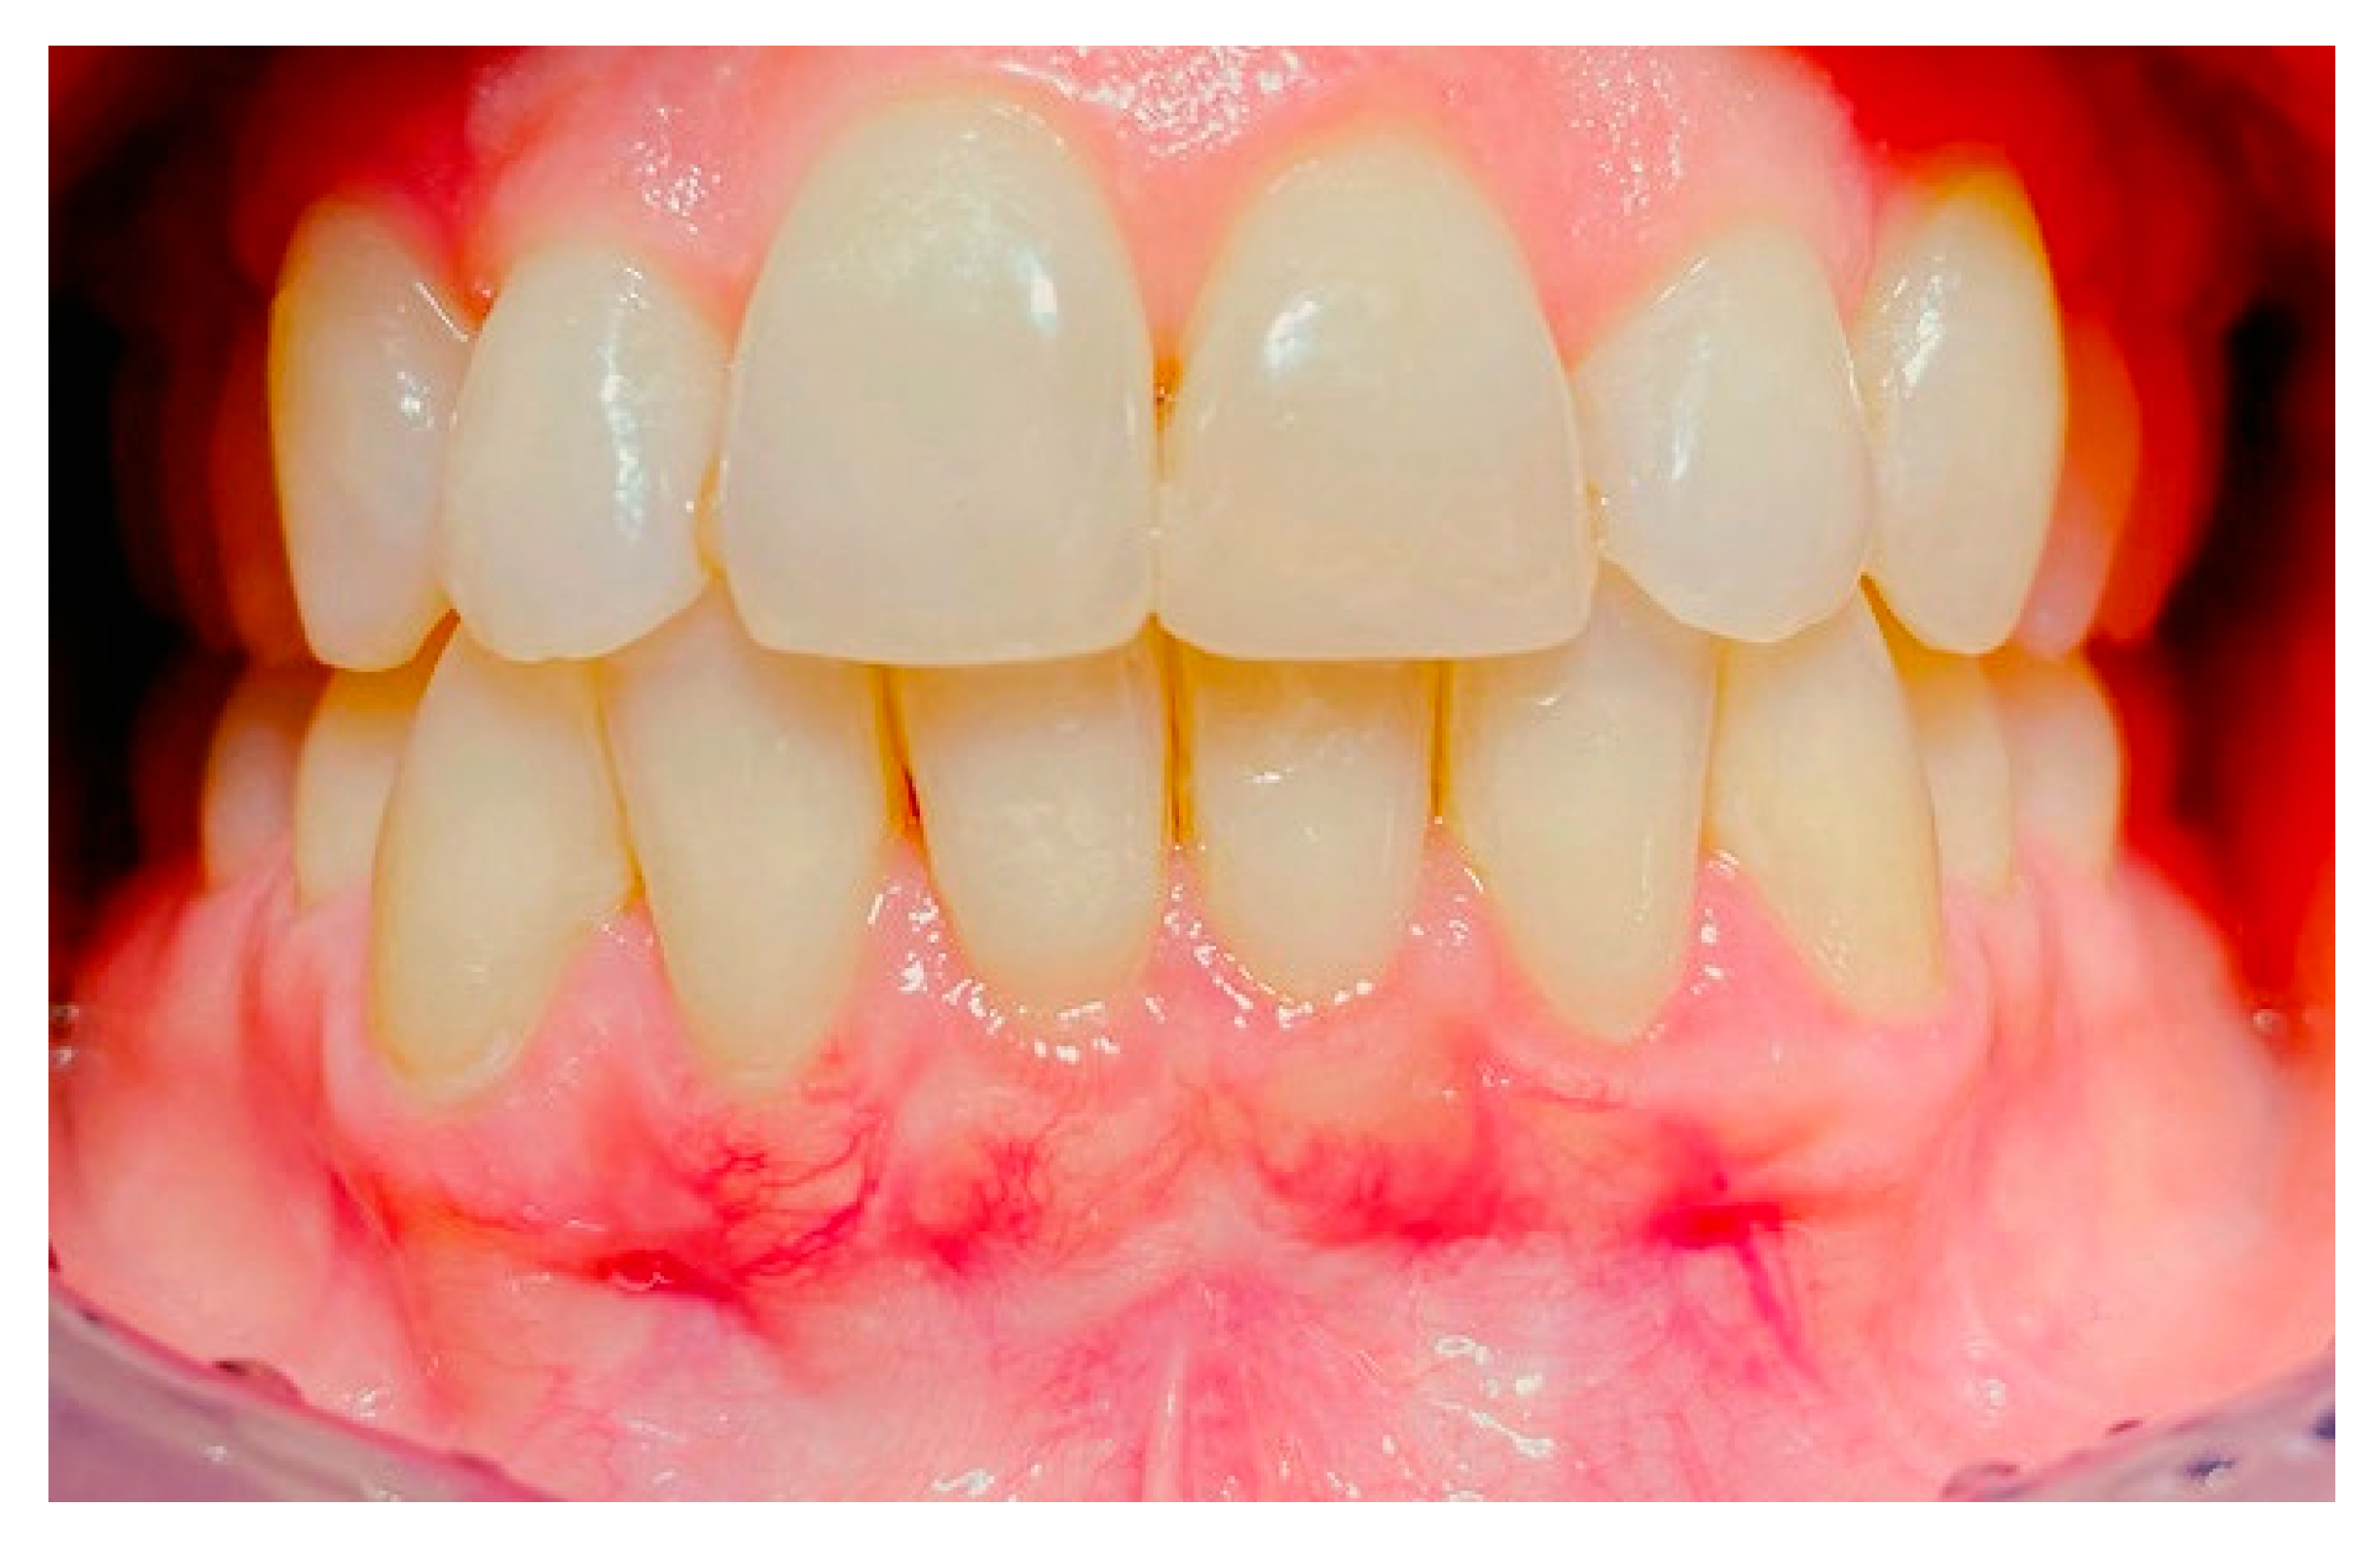

2. Case Study

- (a)

- deep partial thickness incision (blade parallel to the periosteum) made at the level of the external insertion of the frenulum;

- (b)

- elimination of superficial mucous tissue and muscle of the frenulum;

- (c)

- a series of detached points with periosteal anchorage for the apical positioning of the lining mucosa of the lip and the second intention healing of the exposed periosteum.